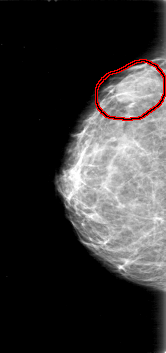

D_4037_1.RIGHT_MLO

RIGHT_MLO LINES 5266 PIXELS_PER_LINE 2476 BITS_PER_PIXEL 12 RESOLUTION 43.5 OVERLAY

FILE: D_4037_1.RIGHT_MLO.OVERLAY

TOTAL_ABNORMALITIES 1

ABNORMALITY 1

LESION_TYPE MASS SHAPE OVAL MARGINS OBSCURED

ASSESSMENT 0

SUBTLETY 4

PATHOLOGY BENIGN

TOTAL_OUTLINES 1

BOUNDARY